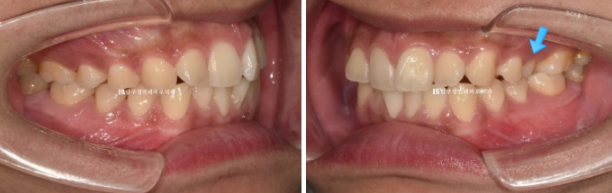

23.12

파란 화살표 어금니는 아래 어금니와 거꾸로 물리는 반대교합 입니다.

23.12~24.10

파란 화살표 반대교합도 해소가 되었습니다